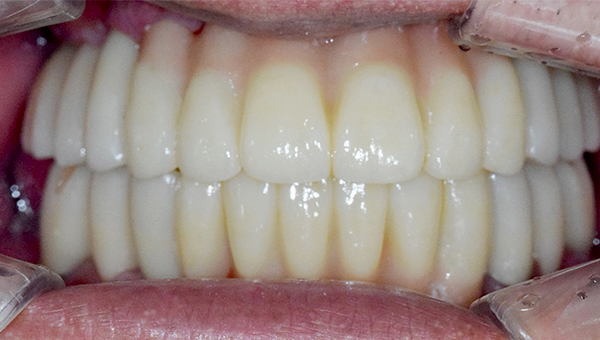

치료사례임플란트

강*란 임플란트 시술 사례

전체 임플란트

2025.02.07

치료 전

2025.08.19

치료 후